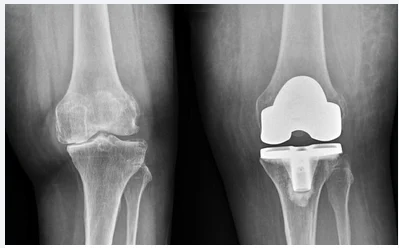

Total knee replacement (TKR), also known as knee arthroplasty, is a surgical procedure that involves replacing the damaged knee joint with artificial implants to restore mobility and relieve pain. Benefits of total knee replacement include:

1. Total Knee Replacement (TKR) – A full knee joint replacement for patients with severe joint damage or arthritis.